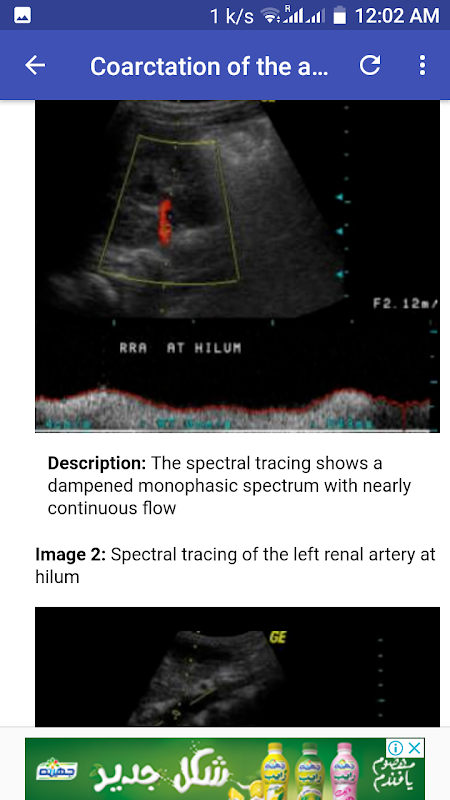

Right ovarian torsion